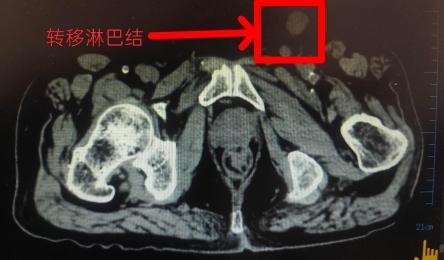

近日,通用环球西安北环医院泌尿外科上演生命奇迹——面对一位高龄且同时患有糖尿病、高血压、脑出血后遗症、偏瘫的阴茎癌合并腹股沟淋巴结转移患者,泌尿外科王珂主任团队以精湛的微创手术技术...